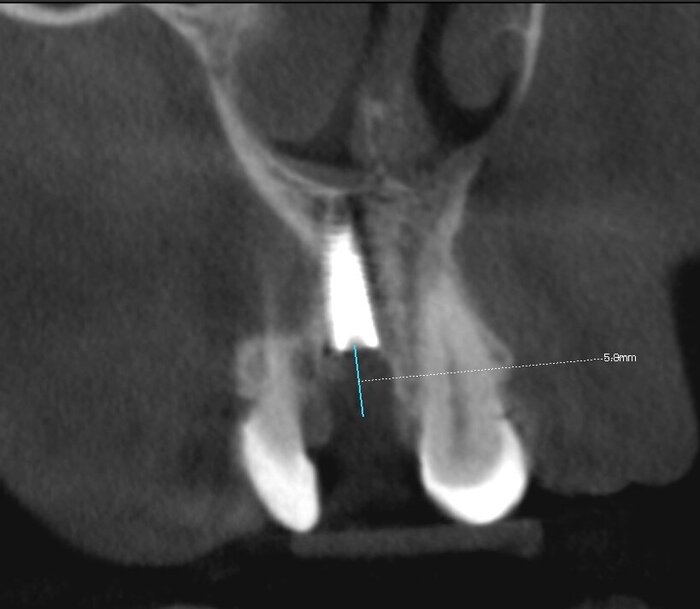

Зуб 1.1, перелом корня.

Зуб 1.1.

Вот в этом "тонком" месте и произошел перелом.

Новости для пациента печальные - такое не лечится. Слишком глубоко проходит линия перелома, слишком сильно поражён корень, слишком велика деструкция кости вокруг линии перелома.

Процессы разрушения корня, судя по всему, шли давно - деструкция коснулась кости. Наблюдаем её дефицит.